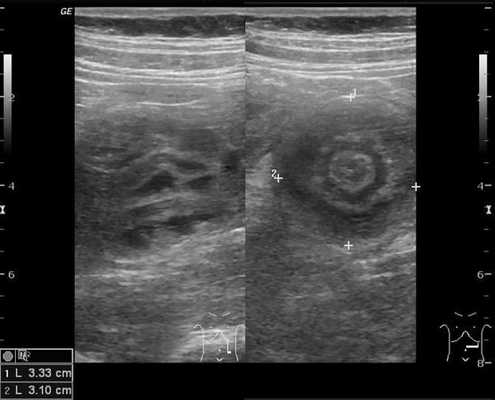

Комментарии: основным методом в дополнительной диагностике инвагинации кишечника является УЗИ органов брюшной полости. Этот метод обладает 100-процентной диагностической достоверностью и специфичностью в отношении инвагинации кишечника. УЗ-признаками инвагинации кишечника является обнаружение симптома «мишени» или «псевдопочки». Симптом «мишени» заключается в наличии на поперечном срезе двух колец низкой эхоплотности, разделенных гиперэхогенным кольцом. Симптом «псевдопочки» виден на продольном срезе и представляет собой наслаивающиеся друг на друга гипер- и гипоэхогенные слои.

На рисунках 2 и 3 отображена ультразвуковая картина кишечной инвагинации.

Рис. 2. Симптом «мишени»

Рис. 3. Симптом «псевдопочки»